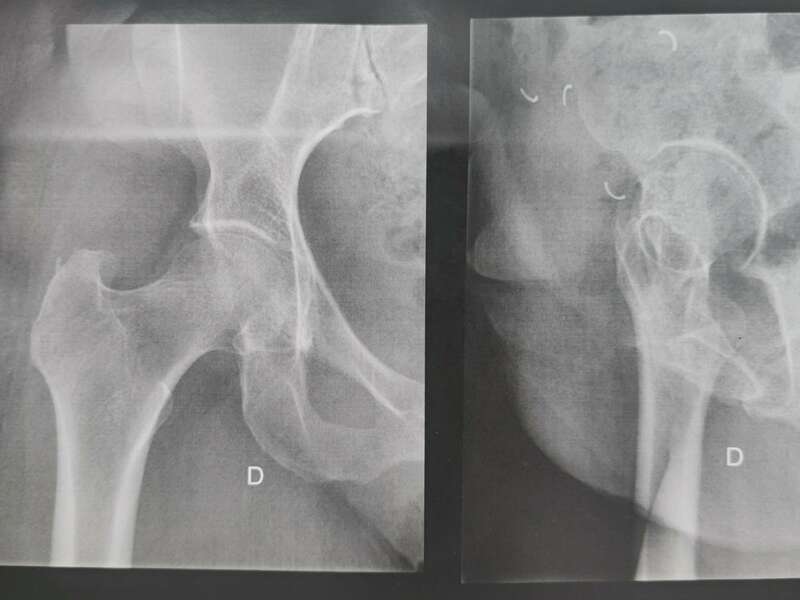

Elle sera confirmée par des examens radiologiques tels que des radiographies de hanche. En cas de doute diagnostic, afin d’éliminer un éventuel diagnostic différentiel, un scanner et/ou une IRM pourront être prescrits.